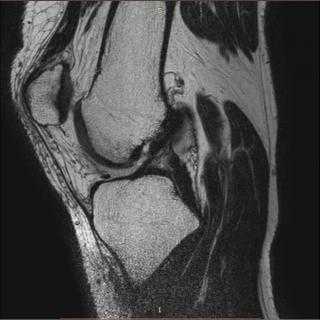

(Слева) МРТ, сагиттальная проекция, режим TV. значительное утолщение сухожилия четырехглавой мышцы с гомогенным сигналом низкой интенсивности, указывающим на экссудат.

(Справа) МРТ, этот же уровень сагиттальная проекция, режим Т2: утолщенное сухожилие четырех-главой мышцы сохраняет низкоинтенсивный сигнал. Экссудат содержит узелковые мягкотканные образования. Этот пациент с хронической почечной недостаточностью получал лечение гемодиализом в течение 18 лет. Отложения и утолщение сухожилия являются типичными признаками диализ-обусловленного амилоидоза (Слева) МРТ, сагиттальная проекция, режим Т1: мягкотканное вещество с сигналом низкой интенсивности в межмыщелковой вырезке, окружающее крестообразные связки и утолщение заднего отдела капсулы. Кроме того, визуализируется эрозия.

(Справа) МРТ, сагиттальная проекция, режим Т2: ткань, занимающая межмыщелковую вырезку, и утолщение заднего отдела капсулы сохраняют сигнал низкой интенсивности. Вещество, характеризующееся сигналом низкой интенсивности внутри сустава, не является специфичным, однако утолщение капсулы подтверждает диагноз амилоидоза.